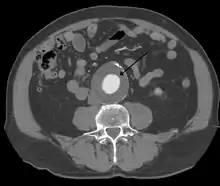

Abdominal aortic aneurysm

Abdominal aortic aneurysms (3,4 cm)

Abdominal aortic aneurysms (AAAs) are more common than their thoracic counterpart. One reason for this is that elastin, the principal load-bearing protein present in the wall of the aorta, is reduced in the abdominal aorta as compared to the thoracic aorta. Another is that the abdominal aorta does not possess vasa vasorum, the nutrient-supplying blood vessels within the wall of the aorta. Most AAA are true aneurysms that involve all three layers (tunica intima, tunica media and tunica adventitia). The prevalence of AAAs increases with age, with an average age of 65–70 at the time of diagnosis. AAAs have been attributed to atherosclerosis, though other factors are involved in their formation.[7]